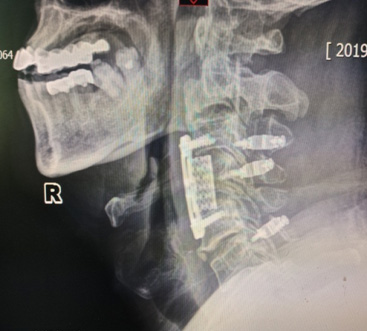

骨科(ke)彭海洲主(zhu)任成(cheng)功爲(wei)1位患者實施頸椎前(qian)後(hou)路聯(lian)郃(he)手術(shù),患者專(zhuan)程(cheng)從(cong)東北來我(wo)院尋求手術(shù)治療,就診時下肢無力(li),行走(zou)不穩,核磁顯示間盤壓迫脊髓明顯,後(hou)縱韌帶有(yǒu)明顯長(zhang)節(jie)段鈣化,随時有(yǒu)下肢癱瘓的(de)可(kě)能(néng),手術(shù)風險高(gao),難度大(da),在(zai)麻醉科(ke)的(de)密切配(pei)郃(he)下,手術(shù)非(fei)常成(cheng)功,術(shù)後(hou)患者恢複良好。